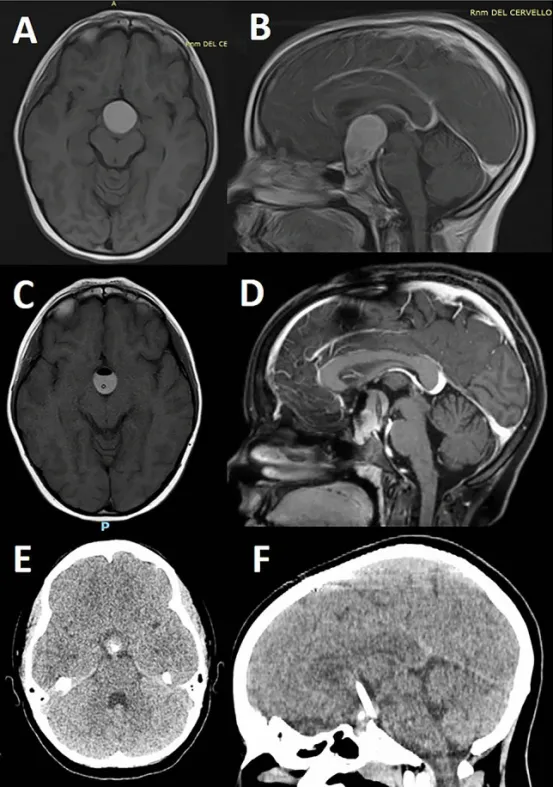

7岁女童的T1加权MRI平扫(图A)及钆对比剂增强扫描(图B)显示存在颅咽管瘤(AC)。增强后可见肿瘤实性部分强化,囊性成分呈典型表现。

介入治疗后影像(图C、D)在导航引导下放置囊内导管并抽吸出典型"机油样"囊液后,复查MRI(图C、D)显示:囊肿体积显著缩小,周围受压结构(如视通路、第三脑室)获得有效减压;囊壁仍可见残留强化,但占位效应明显缓解。

长期随访结果(图E、F)末次随访(4年后,完成3周期腔内治疗/IA后)的CT扫描(图E、F)证实:囊性成分基本消失,仅残留小型、钙化的鞍内肿瘤实性部分;未见囊肿复发或进展征象,提示病情长期稳定控制。